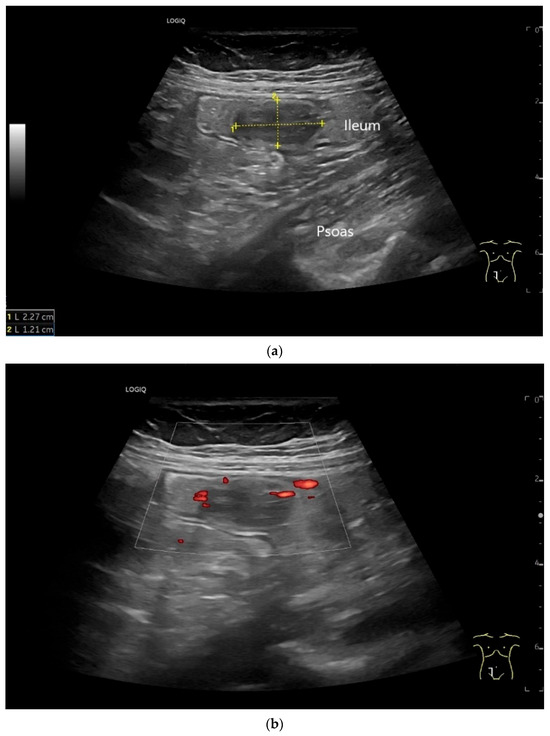

On US, small intestine NEN appear as small focal hypoechoic wall thickenings with a pseudo nodular appearance or as hypoechoic nodular lesion. They are usually small tumors. Adjacent pathological lymph nodes may appear in the mesentery. The tumors extend from the submucosa and may extend into the mesentery via the lamina muscularis propria [90,91,92,93,94,95,96]. NEN are usually well vascularized. Color Doppler imaging (CDI) can show irregular macrovessels in the tumor. Case reports showed that small intestine NETs are hyperenhanced on CEUS [91,92,94,95,96,97] (Figure 7 and Figure 8). Further diagnostics include CT and DOTATOC-PET.

Figure 8.

NET in the ileum. In the terminal ileum, there is a slight wall thickening <5 mm (arrow), but with loss of stratification (a). The tumor (arrow) changes position with peristalsis while the transducer position remains the same. With the 9 MHz linear transducer, the five layers of the unremarkable wall and Kerckring folds (KF) are visible (b). Small vessels can be distinguished in power Doppler (c).